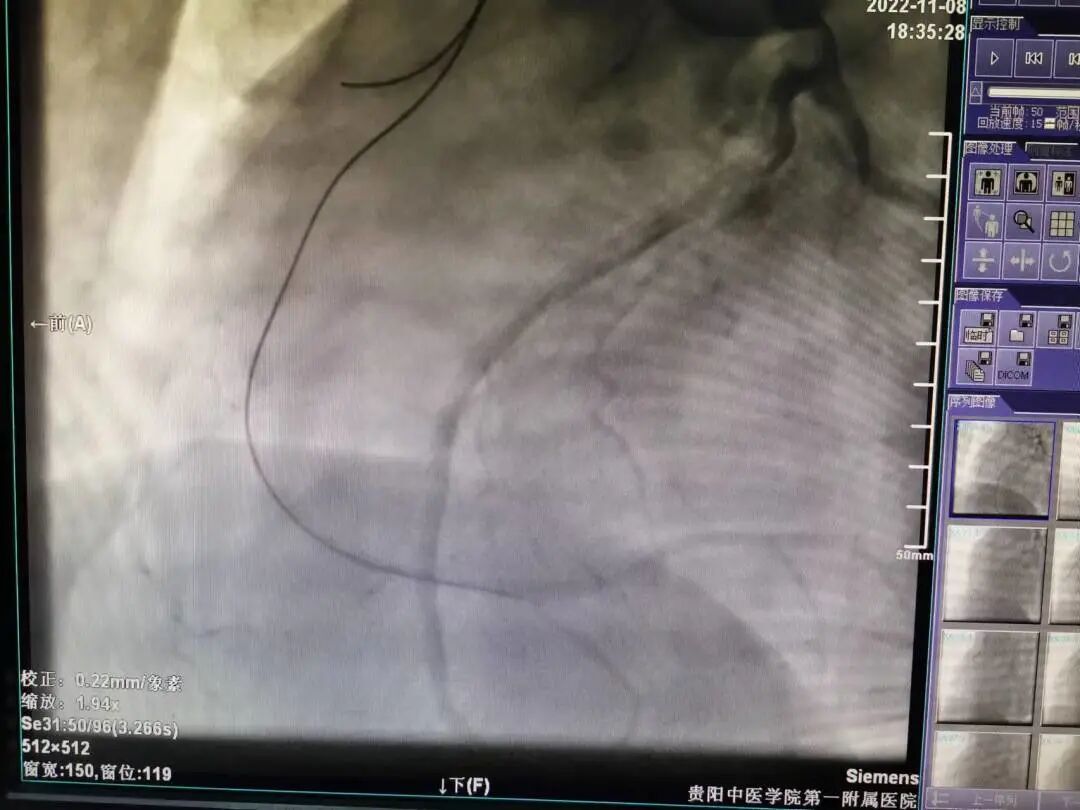

37岁的陈先生,因“胸闷、胸痛4月,加重10天”于11月1日收入我院心血管内科病区,从心电图及心脏彩超结果分析,患者具备冠脉造影的强适应征。郑涛副主任医师仔细查看病人,询问病史、症状,结合体征、检查结果,建议行冠脉造影术,并详细解释手术过程、风险,打消患者顾虑。2022年11月04日行冠脉造影术:术中穿刺右侧桡动脉后造影导管顺利进入左冠脉,造影示左冠状动脉先天性冠状动脉瘘,并可见左冠向右冠远端的逆向血流,而因患者主动脉弓异常扭曲,常规造影导管及专用右冠造影导管反复尝试多次均无法找到右冠脉开口,考虑患者的右冠状动脉开口变异,遂使用猪尾巴导管链接高压注射器造影后隐约显示右冠开口位置,因造影耗时近2小时,为保证患者安全,暂时先下台,准备再次择期手术。

造影导丝是什么再克技术堡垒  巧破闭塞病变——心血管内科应用平行导丝技术救治冠脉慢性完全闭塞患者!_https://www.jmylbn.com_新闻资讯_第3张

左冠脉造影显示左冠向右冠远端的逆向血流